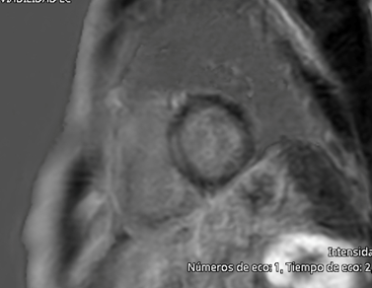

Picture 3 Clinical case CCVG insights Vol13_escardio-hPhotoMedium.png

Figure 3: Cardiac Magnetic Resonance – Late gadolinium enhancement in the mid-myocardium of the interventricular septum.